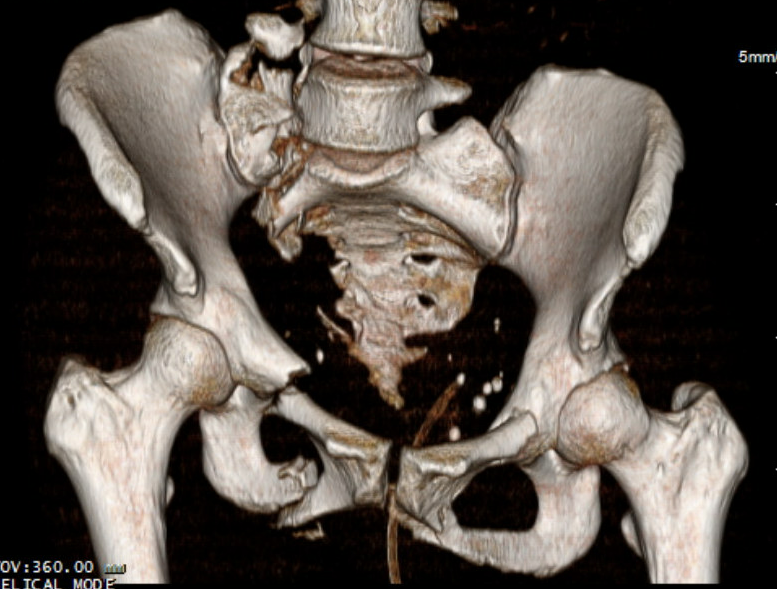

Pathology

Anterior ring

- pubic symphysis disruption

- fracture of the superior and inferior pubic ramus

- fracture acetabulum

Posterior ring

- fracture sacrum / SI joint / ilium